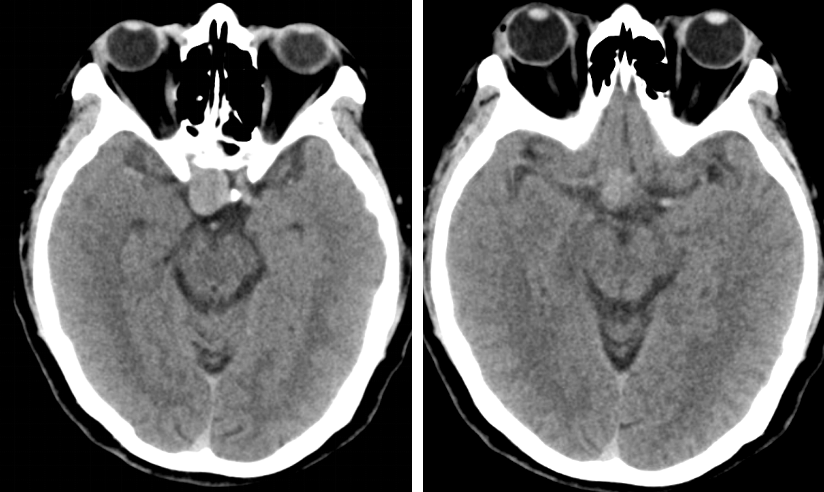

患者约2个月前无明显诱因(否认外伤史)间断出现头痛,头痛为胀痛,左侧较明显,恶心未吐,食欲、睡眠尚可,未予特殊诊治,1个月前患者头痛逐渐加重,思睡,反应略迟钝,行头部CT检查示“慢性硬膜下血肿(双侧)”,于2018年12月15日行颅骨钻孔引流术(左)。术后9天患者恢复良好出院。出院后2周于2019年1月9日患者头痛再次加重,伴有反应迟钝,走路困难,疲乏无力再次就诊,头部CT示“慢性硬膜下血肿(右侧)”,当日再次行颅骨钻孔引流术(右)。术后患者一般状态逐渐好转,无抽搐,无尿便失禁。

头颅CT